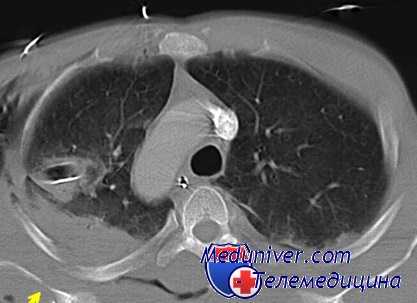

(б) Женщина 33лет, которой была выполнена КТА по поводу тромбоэмболии легочной артерии.

При сканировании в правой паравертебральной области случайно было выявлено мягкотканное объемное образование, гетерогенно накапливающее контрастное вещество.

Также было обнаружено расширение межпозвонкового отверстия на уровне позвонка Th8 и распространение опухоли в спинномозговой канал. При биопсии под ультразвуковым контролем был подтвержден диагноз шванномы.